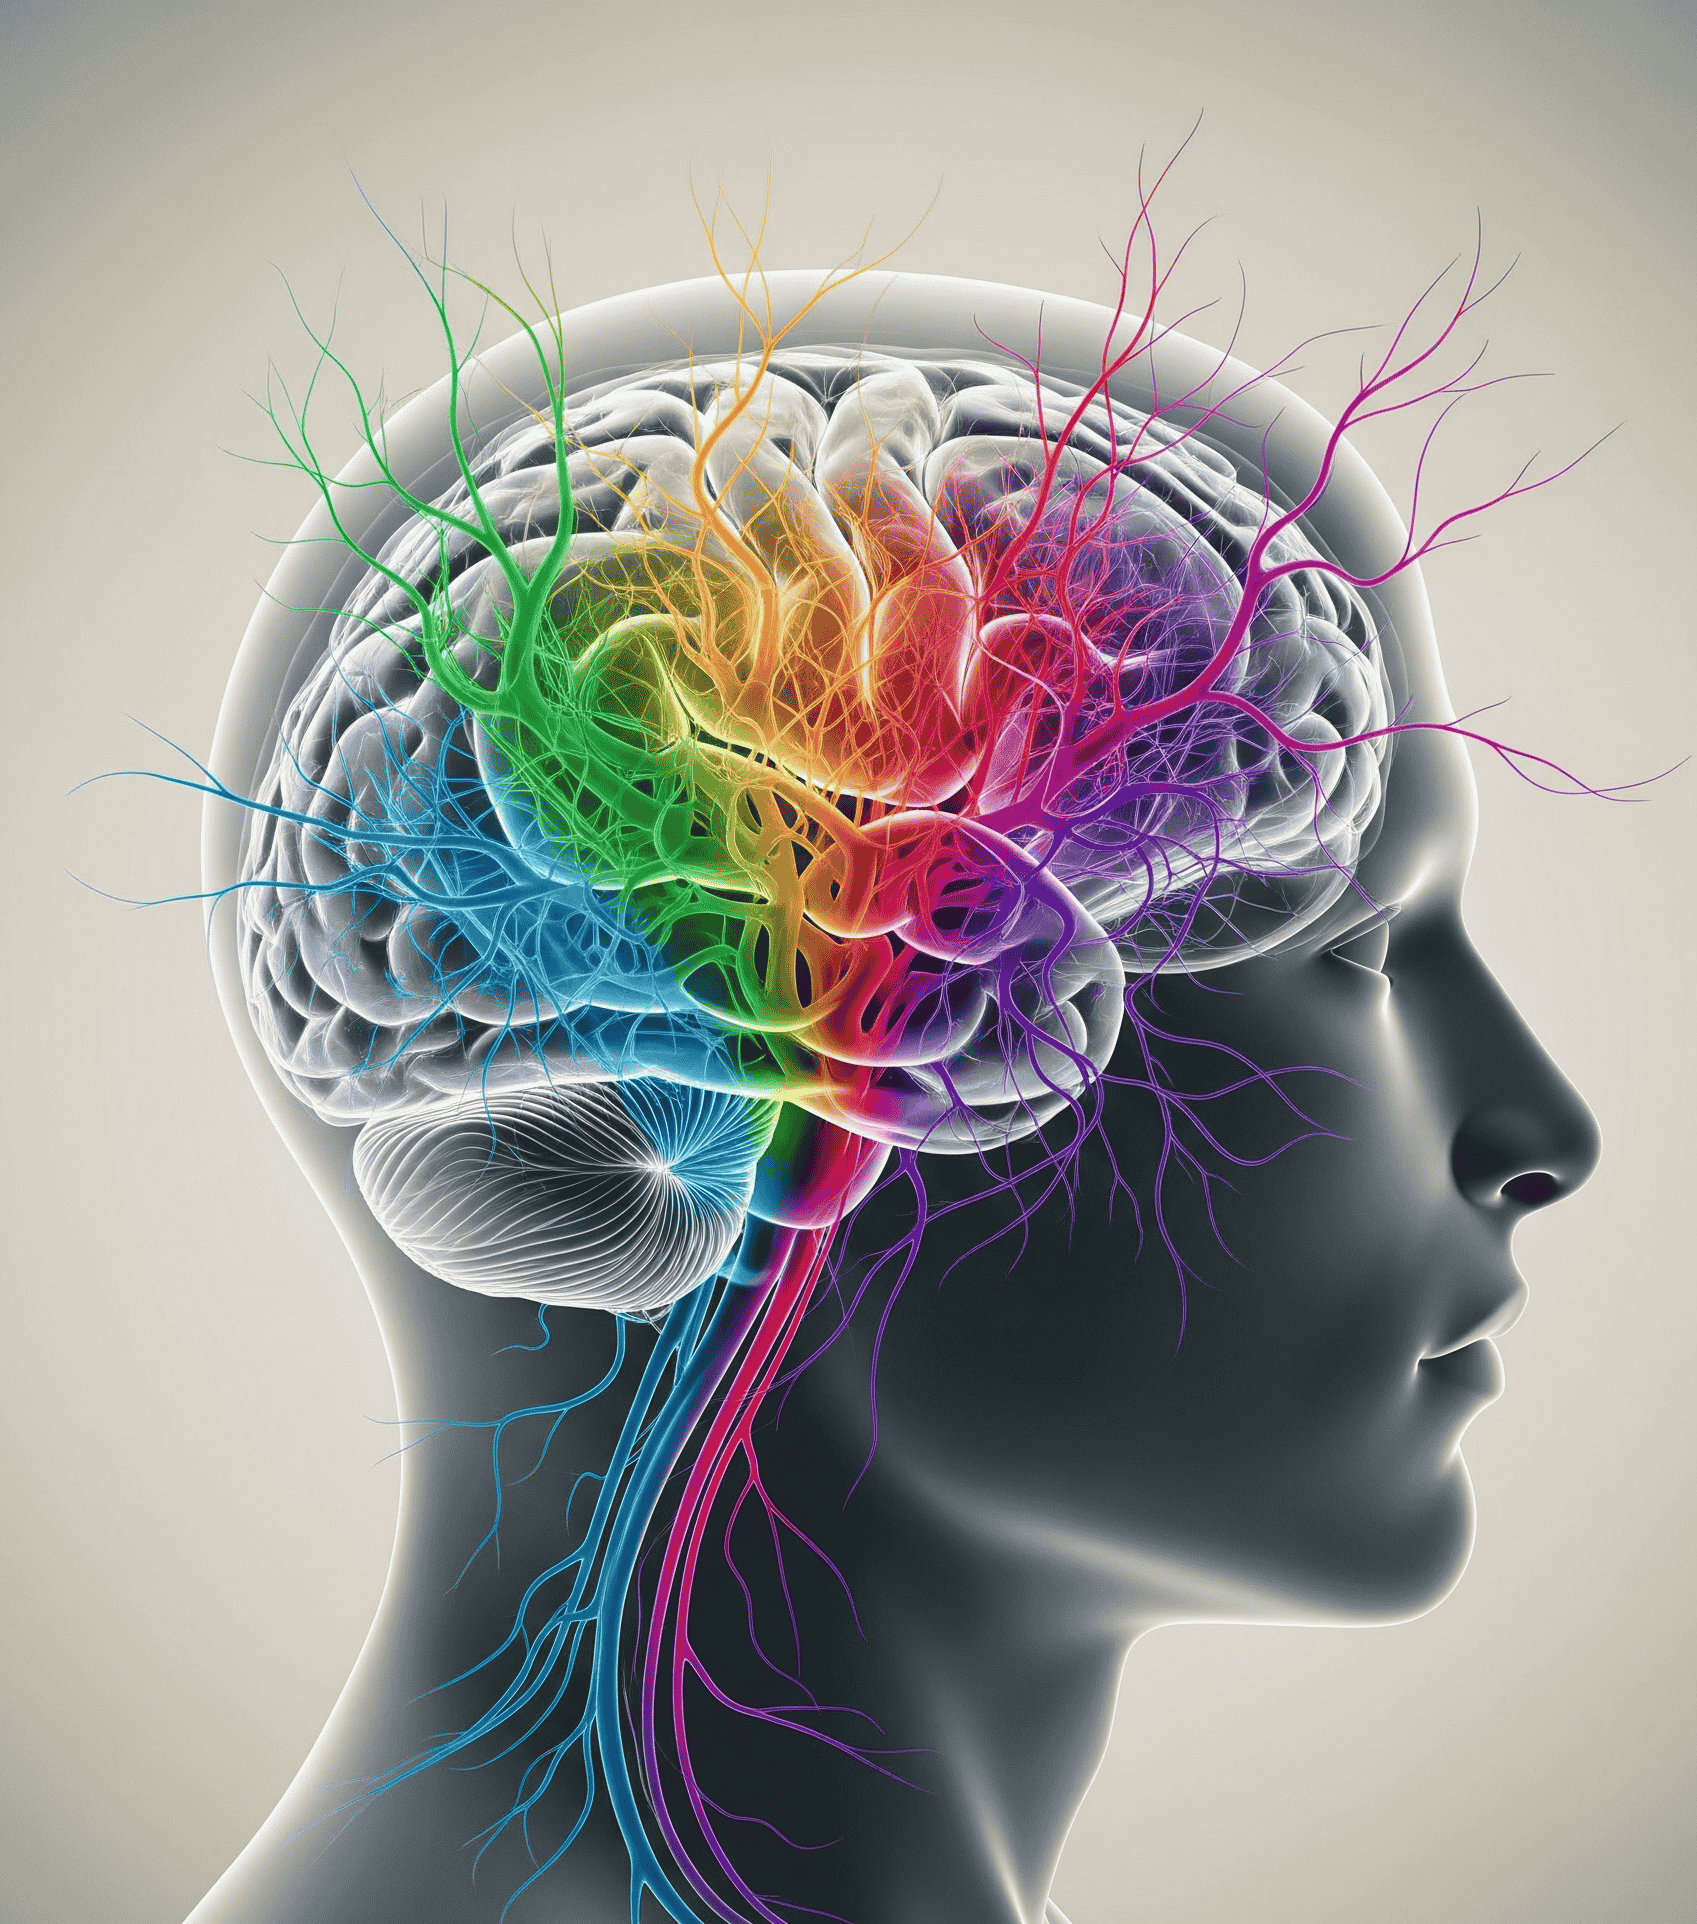

International Journal of Psychopathology & Mind-Brain Modalities

International Journal of Psychopathology & Mind-Brain Modalities is a distinguished peer-reviewed journal devoted to pioneering research at the nexus of psychopathology, neuroscience, and cognitive science...

International Journal of Neuro-Therapeutics & Brain Systems

International Journal of Neuro-Therapeutics & Brain Systems, an Emiko MedTech publication, is a peer-reviewed academic journal dedicated to advancing the scientific understanding and clinical application of therapeutic interventions targeting...